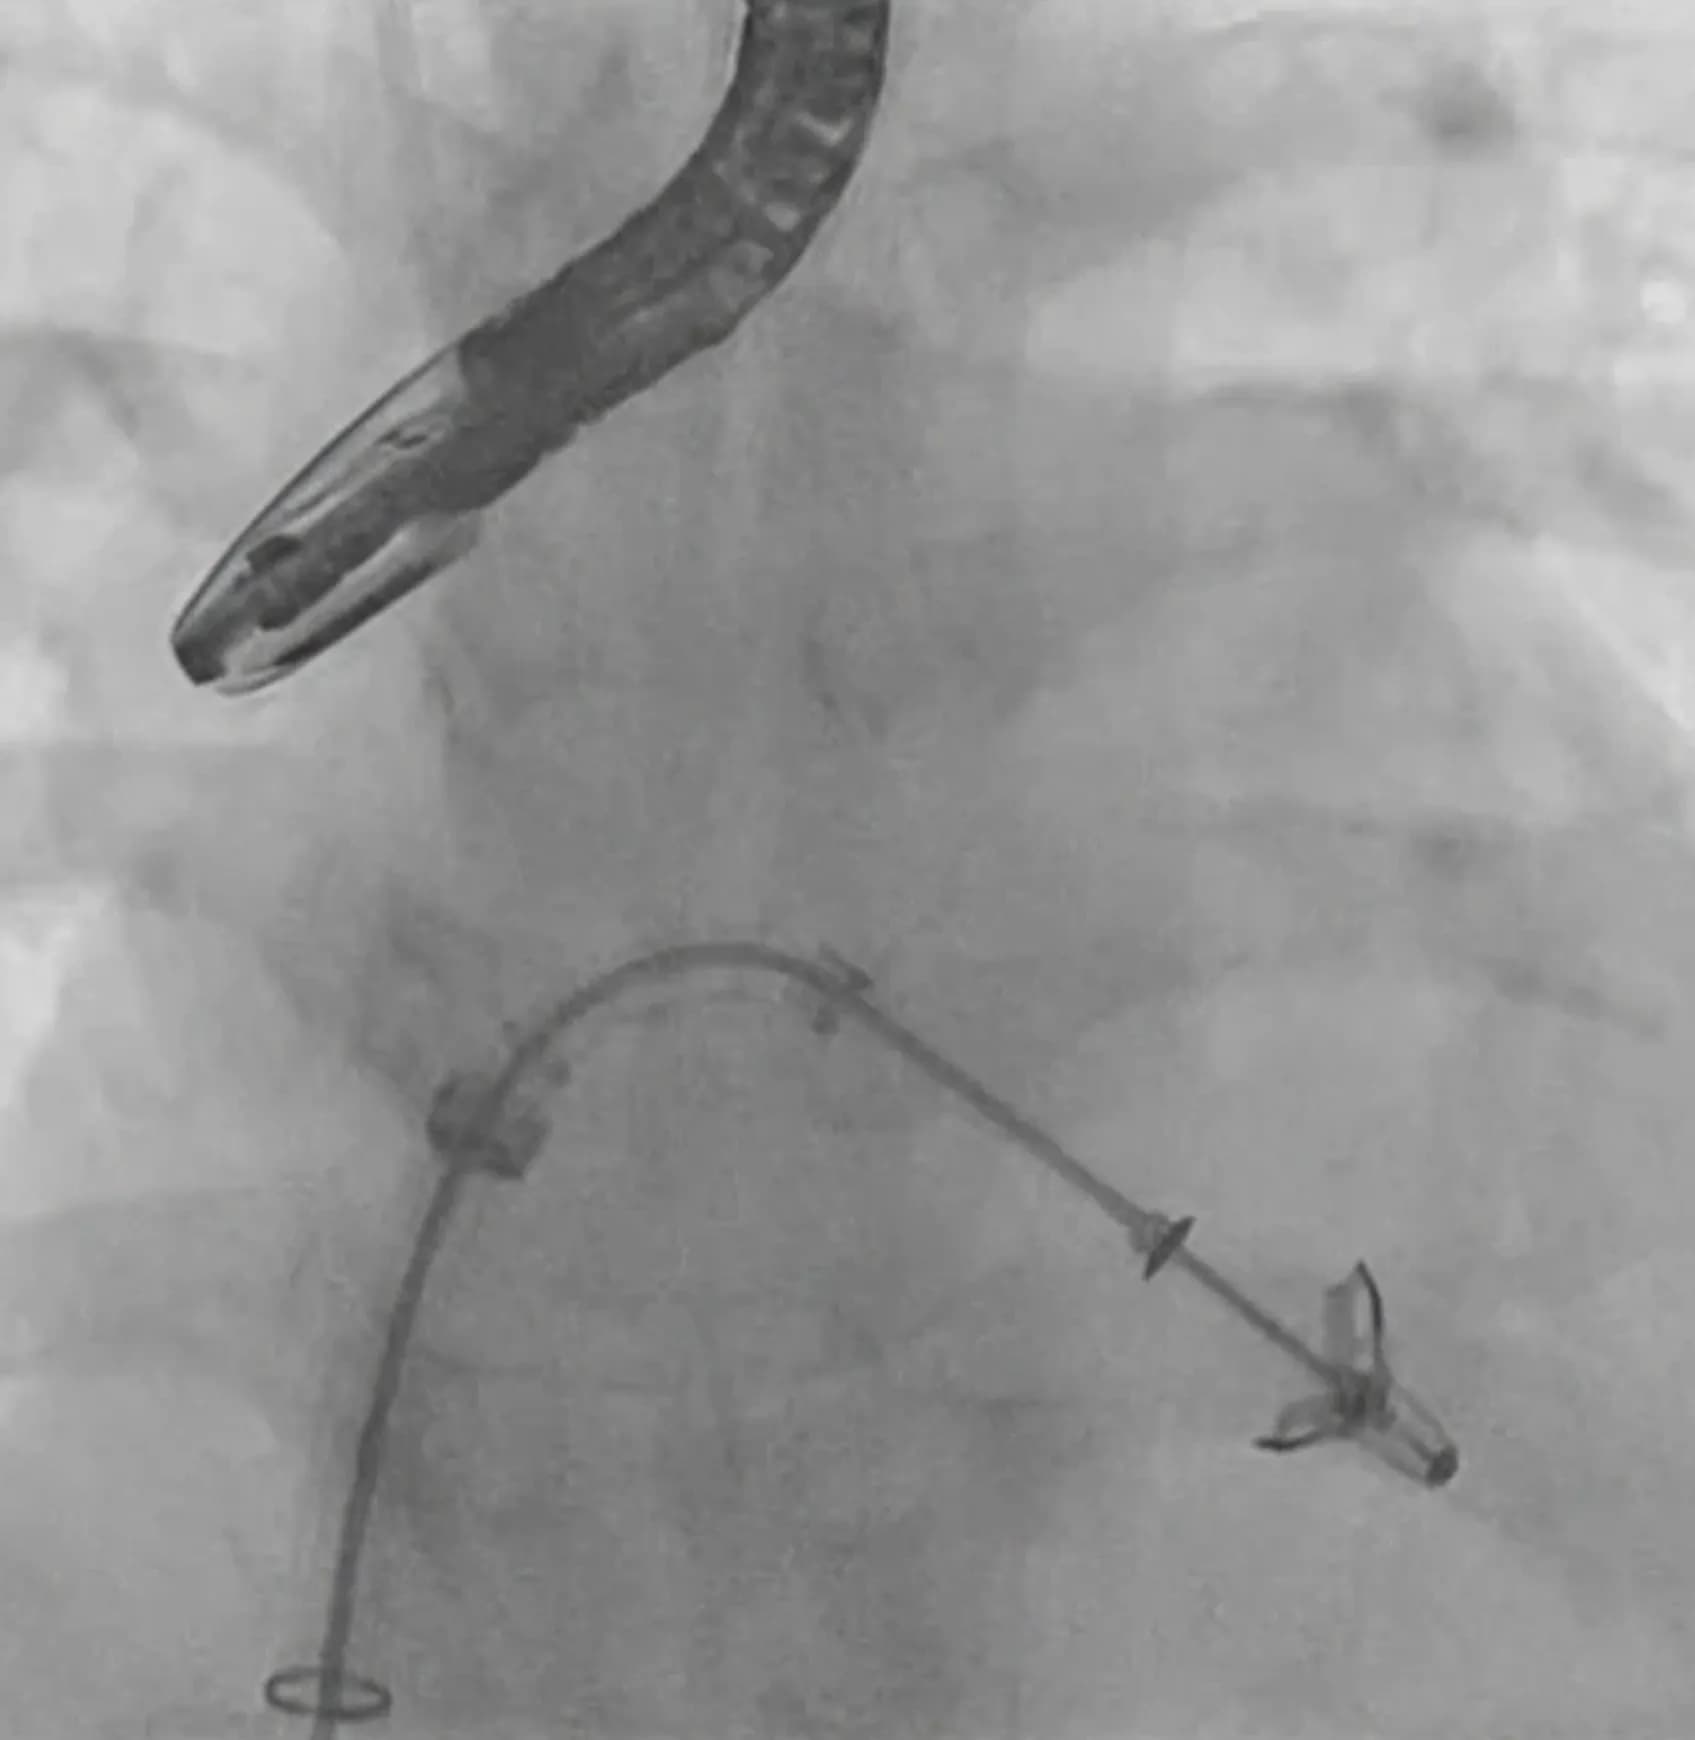

MitraClip is a minimally invasive device used to treat severe mitral regurgitation. It is a form of Transcatheter Edge-to-Edge Repair (TEER), a catheter-based technique designed to reduce mitral valve leakage without open-heart surgery.

During the MitraClip procedure in Mumbai, a small clip is delivered to the mitral valve via a catheter inserted through a vein in the groin. The device helps the valve leaflets close more effectively, reducing leakage and improving symptoms.

For patients considered high risk for open surgery, MitraClip surgery in Mumbai provides a safer alternative with a shorter recovery time.